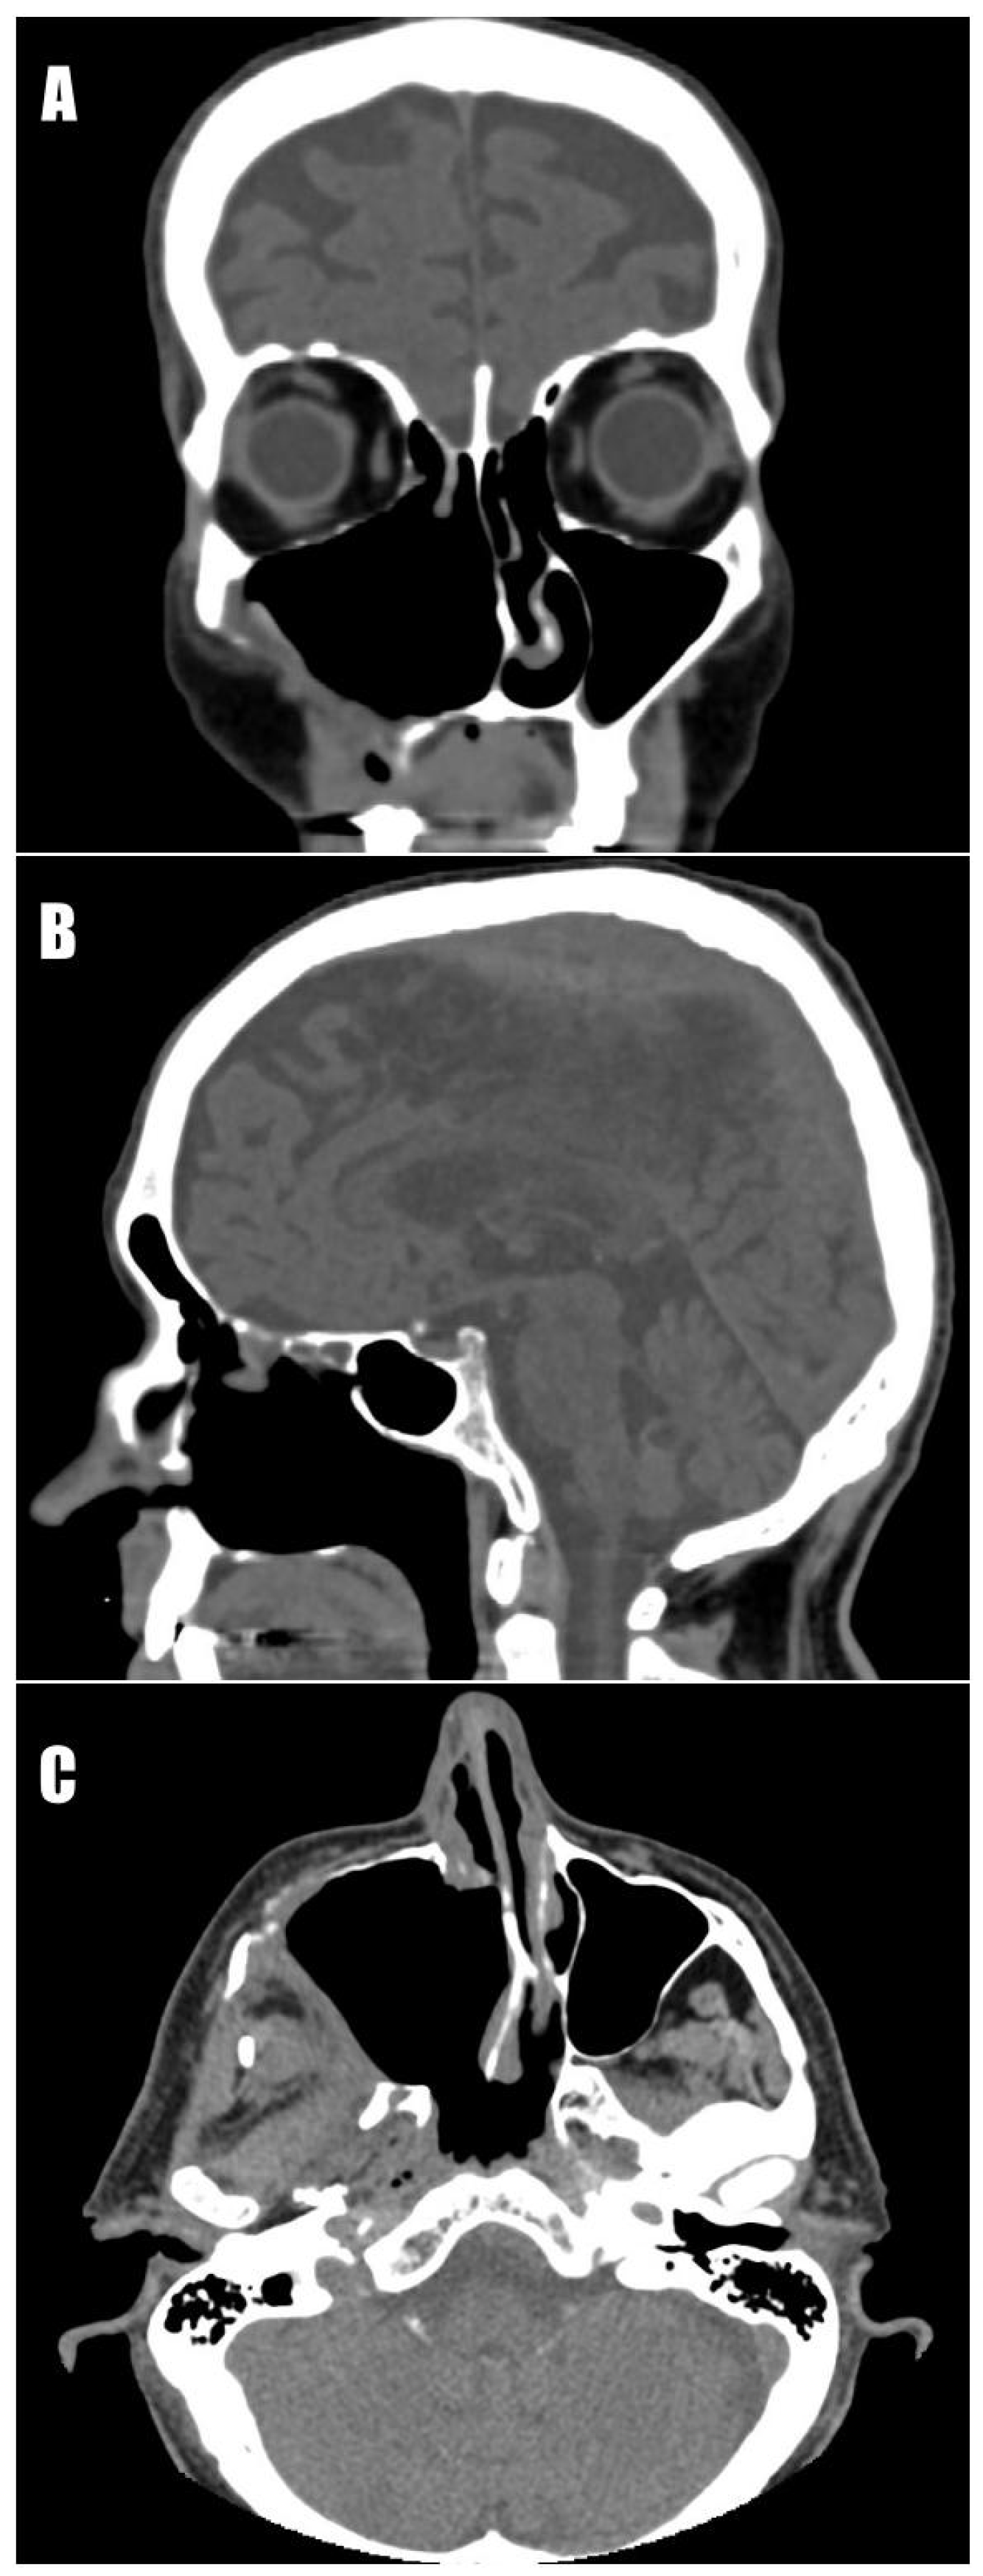

The mass was located near the alveolar process, in the region of missing teeth 14–18, and was expanding into the soft tissues of the cheek and maxillary sinus (Figure 1). Upon physical examination, protrusion of the eyeball, narrowing of the right nasal passage, and asymmetry of the face were observed. Apart from changes within the maxillofacial area, ascites and ulceration on the left shin were noticed.

Due to suspicion of a neoplastic process, computed tomography (CT) of the head, neck, chest, abdominal cavity, and pelvis was performed. CT of the maxillofacial region revealed a pathological tissue mass (51 × 43 × 56 mm) with heterogeneous shadowing and hemorrhagic areas. It showed heterogeneous solid contrast enhancement, occupied the right maxillary sinus with an expansive growth pattern, and widened the sinus contours in every direction (Figure 2). On the right side of the neck, enlarged lymph nodes of groups Ib (up to 12 mm on the short axis), IIa (up to 11 mm), and V (up to 10 mm) were observed. On the left side, lymph nodes were not present. Additionally, inflammatory mucosal changes within the ethmoid sinus and the ostium of the right frontal sinus were visualized. The increased density of the right parotid gland was noted, with possible inflammatory changes. In the differential diagnosis, invasive fungal infection; odontogenic cysts; and neoplastic processes, including malignant mesenchymal tumors, were considered [10].

Figure 2. Computed tomography scans. (A) Frontal section. The pathological mass extended into the buccal soft tissues and the nasal cavity, destroying the nasal conchae. (B) Sagittal section. The tumor diminished the right orbit. Mass invasion into the oral cavity at the level of missing teeth 14–18 is visible. (C) Axial section. The lesion protruded into the soft tissues, causing asymmetry in the right cheek.